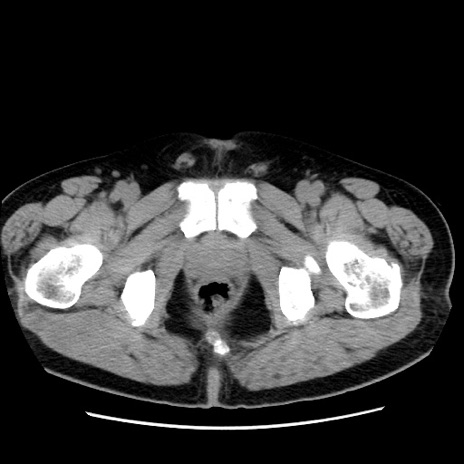

症例16(横断像)

【症例】 70歳代男性

【主訴】 腹痛、嘔吐

【現病歴】 約1ヶ月前より間欠的に腹痛と嘔吐あり、当院消化器内科を受診したところCTで多発する肝臓のLDAを指摘され、精査中であった。以降は消化器症状は安定していたが、2日前より嘔気と腹痛があり、同日より排便・排ガスが消失した。改善認めず、 本日、救急外来を受診した。

【既往歴】 大腸ポリープ切除後。

【身体所見】意識清明・会話良好、BT 36.3℃、BP 127/80mmHg、 P 80bpm、腹部:膨満あり、平坦・軟、上腹部正中および下腹部正中に圧痛あり、反跳痛なし、筋性防御なし。

【データ】WBC 7200、CRP 0.77